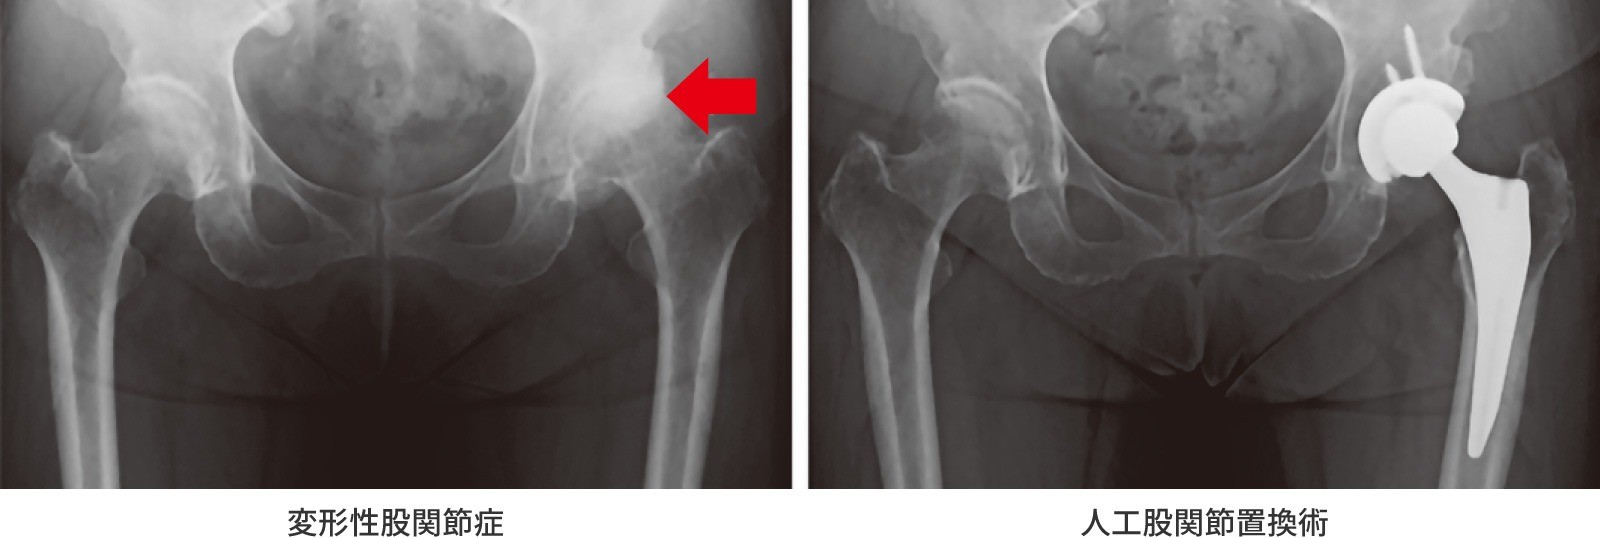

股関節は、立つ・歩く・座るといった日常生活を支える大切な関節です。しかし、加齢や長年の負担、体重増加、骨盤の形などが原因で股関節の軟骨がすり減り骨同士がぶつかり合うことで痛みや動きの制限が現れます。これが『変形性股関節症』です。患者さんの多くは女性で、日本人の殆ど(約8割)は大腿骨を覆う骨盤の被さりが浅い臼蓋形成不全がその原因です。

症状は、初期では「少し痛む」「休むと楽になる」 程度ですが、進行すると爪切りや靴下を履くのが難しい、階段や車・バスの乗り降りに手すりが必要になるなど日常生活にも支障が出てきます。さらに痛みが強くなると、夜間痛や歩行障害にもつながります。ただし痛みの場所に注意が必要です。放散痛といって脚の付け根だけでなく太もも・膝・腰に痛みを感じることがあるため、痛みの原因が股関節と気が付かないでいることもあります。簡単な見分け方として、あぐらをかこうとした時に痛みを感じたら股関節が原因かもしれません。病院やクリニックでは、問診や診察の後にレントゲン写真で軟骨のすり減りや関節の変形をみて診断します。

手術は、手術以外の方法でも症状が取れないときに考えます。一般的に行われるのは人工股関節置換術です。現在日本では年間78,000件以上行われています。痛みの原因となる関節を人工物に入れ替えることで、痛みをとる効果と機能改善効果が期待できます。最近では人工関節が入っていることを忘れて日常生活を送れることが治療目標と言われています。